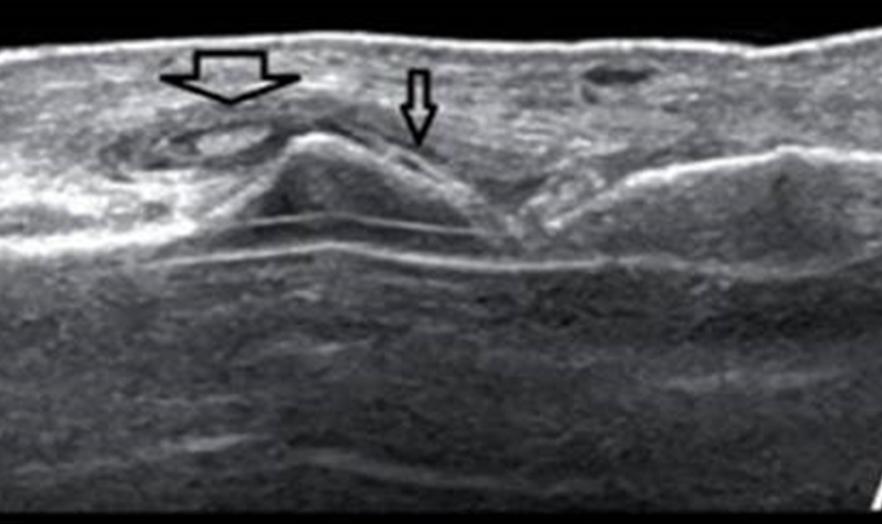

双腕、手及双足部分关节周围可见软组织不对称结节肿胀,密度稍增高;部分关节面下及边缘见部分囊状、穿凿样骨质破坏。

影像学检查对诊断痛风,评价病情有很大帮助,该患者双源CT,超声及X线均显示典型痛风改变,临床医生应合理应用这些敏感特意的影像学手段诊断、管理痛风。